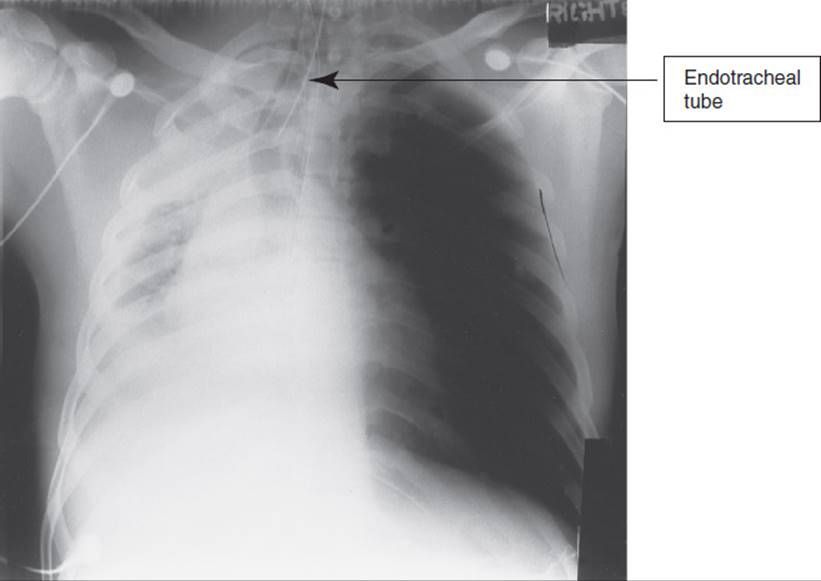

Ventilator-associated pneumonia (VAP), the most frequent type of nosocomial infection in the ICU, occurs in up to 30% of intubated patients.89 VAP consists of a pulmonary inflammatory reaction and sepsis in patients who are mechanically ventilated for a minimum of 48 hours. It is difficult to accurately diagnose, and because the underlying illness of critically ill patients often has a high mortality rate, it is difficult to differentiate to what extent mechanical ventilation contributes to the risk of nosocomial pneumonia.90 Historically, clinical findings have been used to diagnose pneumonia yet have not been shown to have sufficient accuracy, leading to the overuse of antimicrobial therapy (Table 19-7). Quantitative cultures are recommended to determine the bacterial load in a tracheal sample to differentiate colonization from infection and avoid overutilization of antibiotics. Clinicians may also see the use of biomarkers to assist in the diagnosis of VAP in the future.89

TABLE 19-7 Criteria for the Diagnosis of Pneumonia